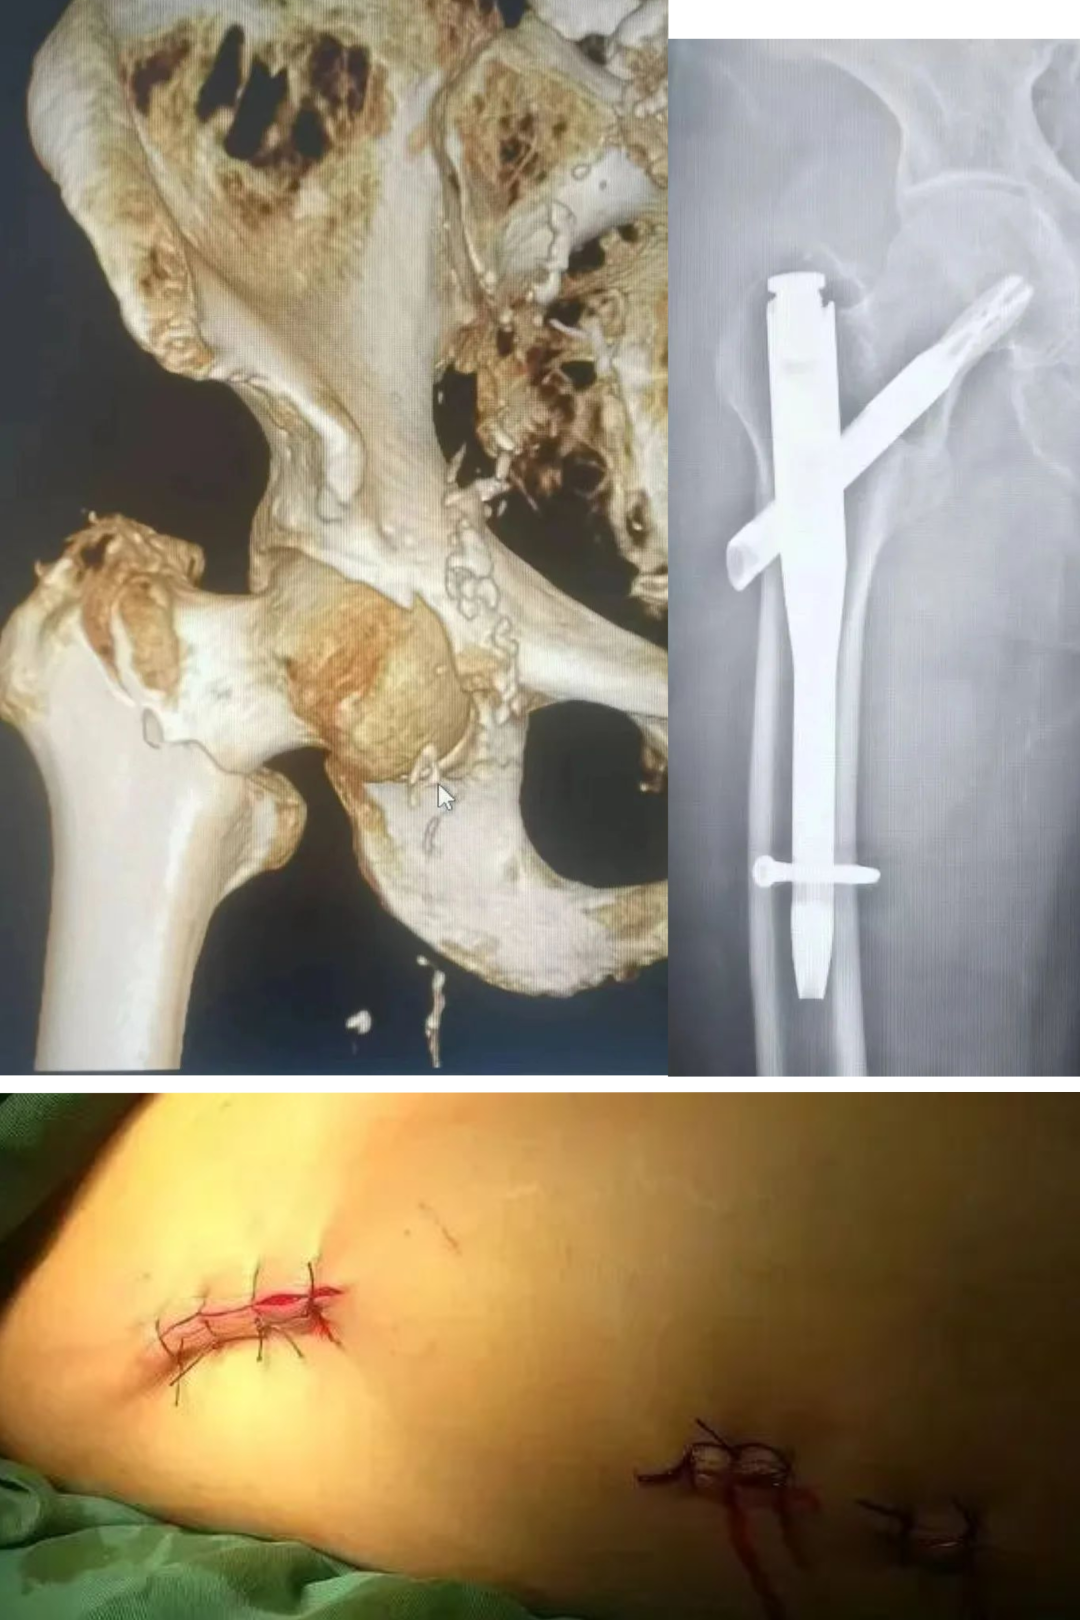

2. 取出风险过高的部位

骨盆、脊柱、髋臼等:这些地方解剖结构复杂,神经血管丰富,取出手术风险大、创伤大、出血多,而收益有限,通常不建议取出。

肱骨干、股骨颈等:部分位置取出时可能损伤重要神经(如桡神经),或造成二次骨折。